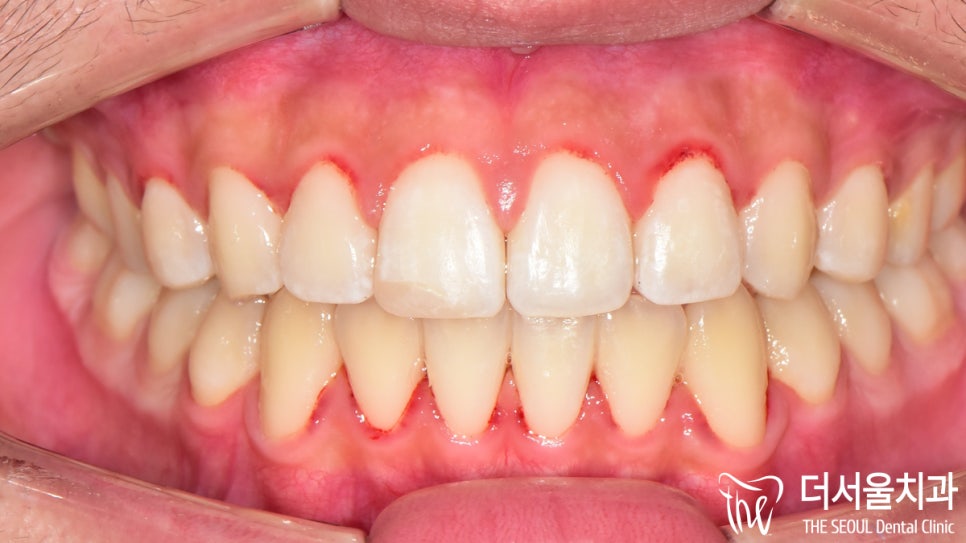

지금 현재 상태를 파악해 보니

토끼 이빨을 갖고 있어서 교정을 하고 싶은데

이갈이 까지 함께 개선을 하고 싶다!

이 말씀이신거 같은데요.

우선 현재 상태를 확인해 보기로 했습니다.

이와 더불어 톡 튀어나와 있는

토끼 이빨이 관찰되고 있는데요.

측면 세팔로 사진에서 볼 수 있듯이

돌출감이 꽤 느껴지고 있었습니다.